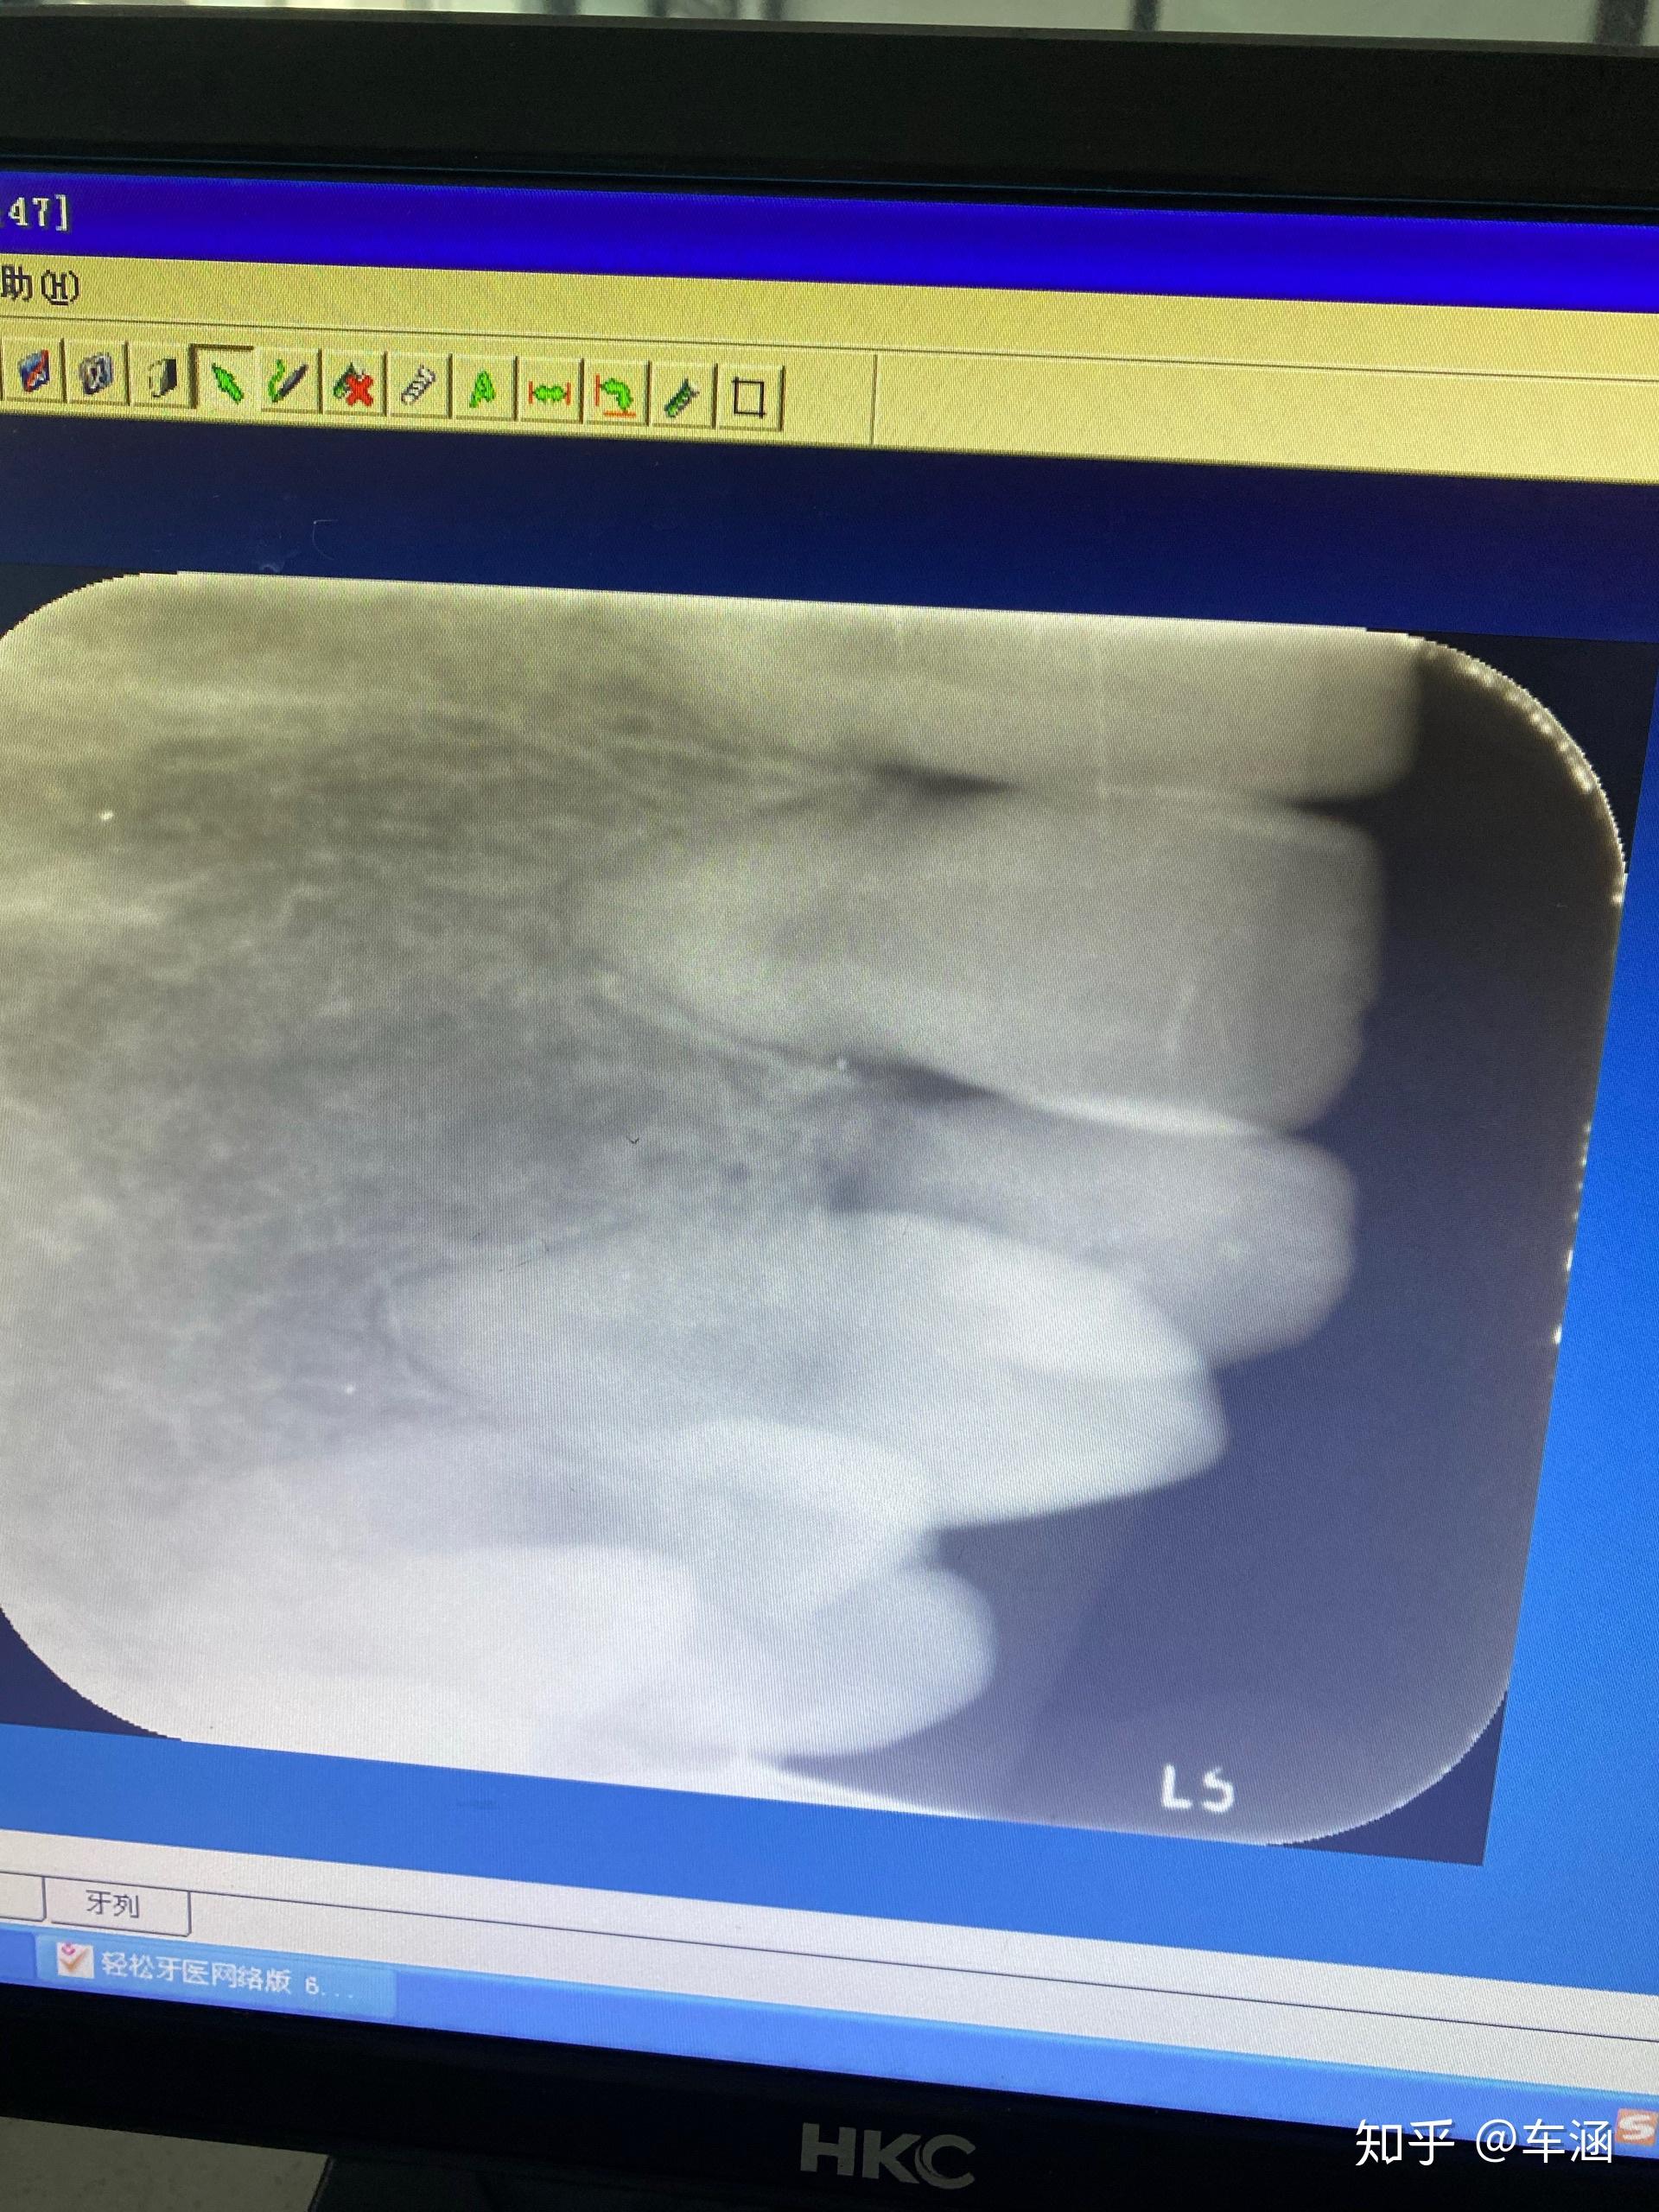

想问下大家我的牙根短吗

图片尺寸1080x810